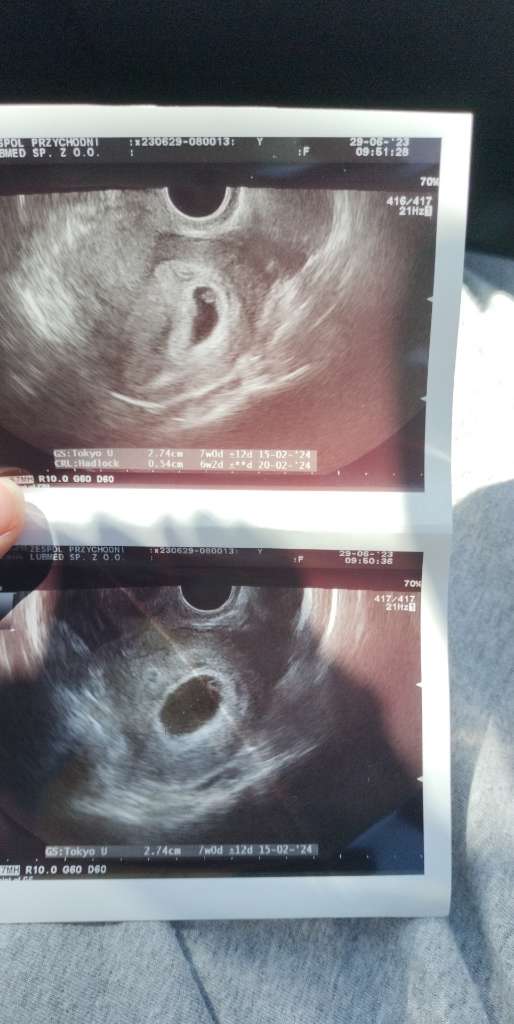

A ja jednak poszłam na tą wizytę mimo że odwołałam to było miejsce i jeszcze dzisiaj brak bólu piersi i stres idę . Wiem że nie miała super USG ale widziałam zarodek i serduszko więc ciąża żywa ❤️

Pani dr nie puszcza serduszka niestety nie zmierzyla jak bije jak to powiedziała że na tym etapie nie jest to potrzebne ok nie kłóciłam się 😀

Mówiła że ciążę teraz się opiera na wielkości pęcherzyka ciążowego czyli u mnie się zgadza jest 7+0 a zarodek na 6+2 ale dodając USG serio miała nie najlepsze to czekam na wizytę 07.07 i wtedy powinno się wszystko rozwinąć ❤️

O.50 cm szczęścia 😍

Chyba takie odchylenie na tym etapie to normalne wg @ 7+1 ?